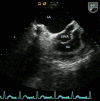

Figure 1

Transesophageal echocardiography showing sinus of Valsalva aneurysm from left coronary sinus rupturing into right atrium. LA, left atrium; RA, right atrium; LSVA, left sinus of Valsalva aneurysm rupturing into right atrium.